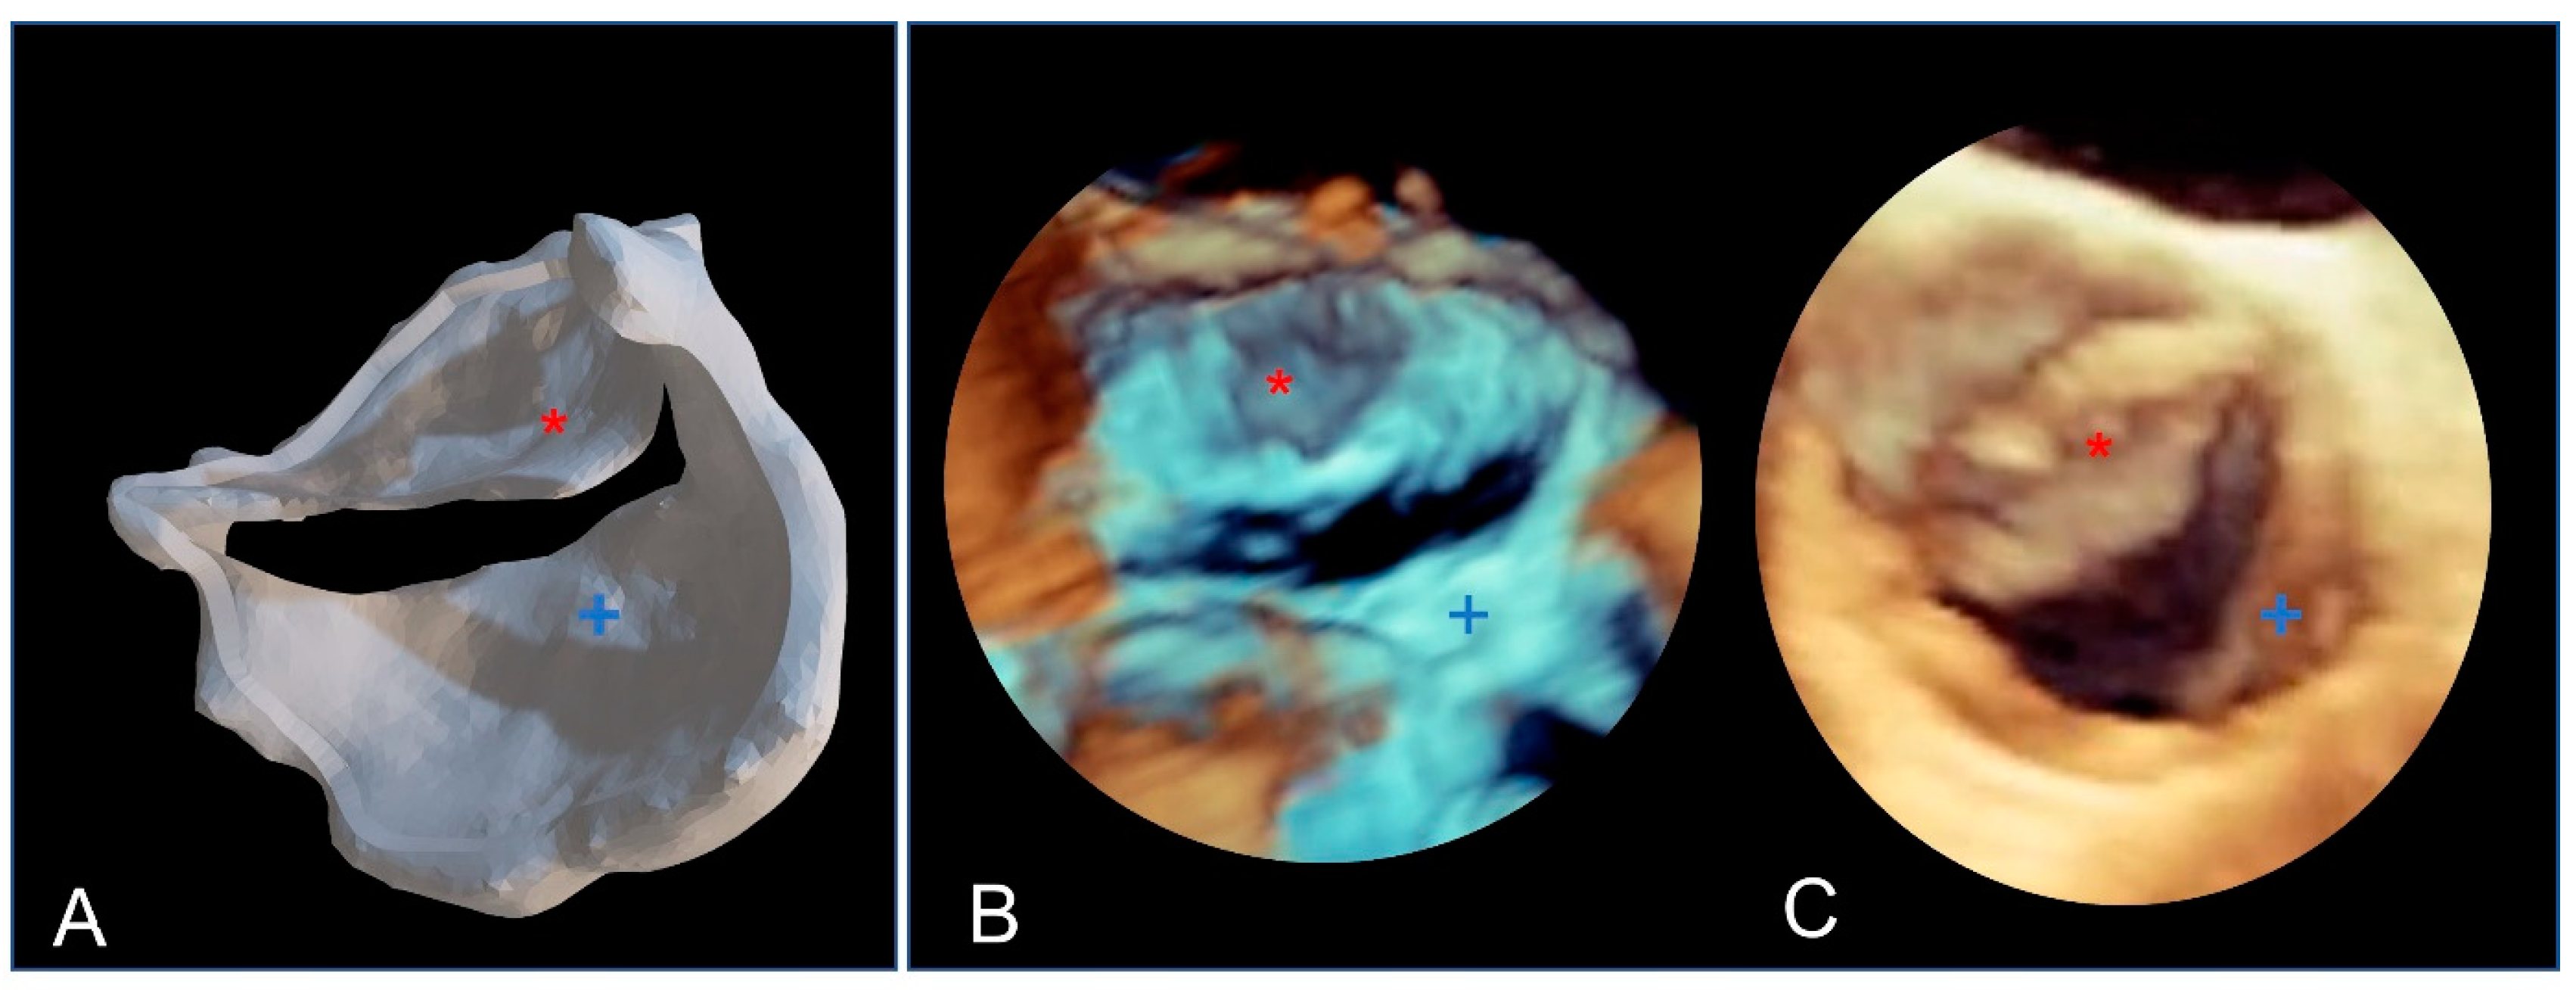

Due to their porous structure, the TPU and TPE models exhibit interesting echogenic properties. We compared the echogenic rendering with in situ images of the same valve (refer to Figure 9 and Figure 10). The valve structure was accurately depicted in both 3D and 2D views. Notably, the cusp in situ thickness measurements align with the model’s 0.3 mm thickness.

Figure 9.

The bicuspid aortic valve in a similar face-plan view. (A) View of the 3D printed model. (B) A 3D ultrasound view of the immersed model (with two thin aortic cusps marked with * and +). (C) A 3D ultrasound in situ view of the same valve in the patient, showing both cusps (+ and *).